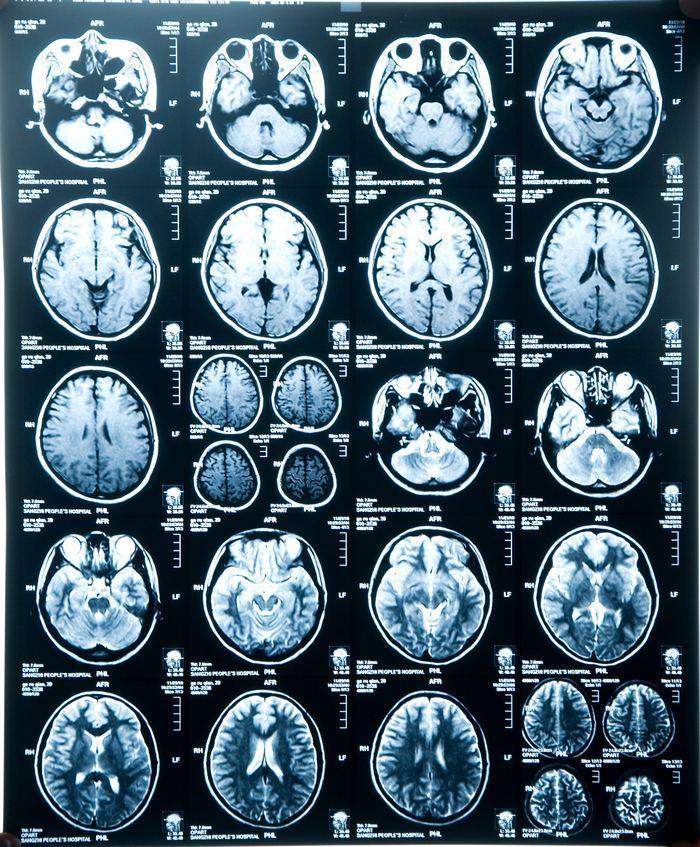

轻度脑萎缩

轻度脑萎缩,脑萎缩吃什么药最好

其他无明显症状,这是去检查脑部的影像,医生诊断脑萎缩.请懂的帮忙

正常大脑和脑萎缩图片

脑萎缩ct

脑萎缩核磁

脑萎缩图片

脑萎缩ct表现

脑萎缩图片对比

脑萎缩ct图片

脑萎缩的ct表现及图解

脑萎缩ct片子图片

脑萎缩ct图片解说